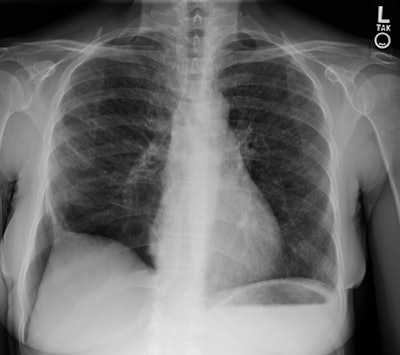

The patient shown below presented with chest pain and shortness of breath. The CXR revealed coarsened, prominent lung markings with a predominantly subpleural right pneumothorax. (Click image to enlarge)